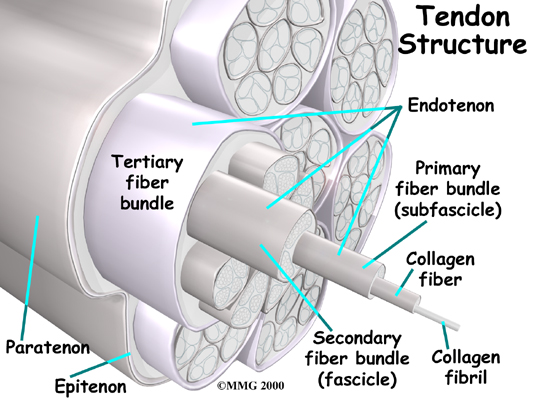

Tendons are made up of strands of a material called collagen. Think of a tendon as similar to a nylon rope and the strands of collagen as the nylon strands. As we age, or repetitively use the tendon, some of the individual strands of the tendon can degenerate, lose normal arrangement due to the degeneration, or break, and the tendon loses strength.

Problems with the posterior tibial tendon seem to occur in stages. Initially, irritation of the outer covering of the tendon, called the paratenon, causes paratendonitis. This means that there is inflammation between the lining of the tendon and the tendon itself where it runs through the tunnel behind the medial malleolus. This tendonitis can start a process of wear and tear on the tendon fibers.

As the tendon heals itself from wear and tear, scar tissue forms, thickening the tendon. This process can continue to the extent that a nodule, or knot, forms within the tendon. Once the painful tendon has changed in structure, the term tendonosis, rather than tendonitis, is used. Unlike with tendonitis, recent evidence shows that inflammation is not present with tendonosis. The area of structural change in the tendon is weaker than normal tendon. The weakened tendon sets the stage for the possibility of rupture of the tendon.